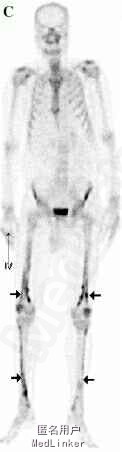

胸部CT提示左肺巨大肿物(图A),痰液细胞学检查示腺癌阳性。另外,患者诉双下肢疼痛,X线检查显示右股骨可见骨膜反应(图B)。骨闪烁显像示双侧股骨及胫骨弥漫皮质摄取(图C),符合肺性肥大性骨关节病(HPOA)。

HPOA是一种通常与肺癌相关的副癌综合征,特点为杵状指、关节炎、肢体疼痛及长骨骨膜炎。其中骨膜炎是HPOA的特征性表现,X线检查常可见对称性骨膜反应,受累部位多见于长骨的双侧干骺端和骨干,这与骨转移有所不同。 DOI: 10.2169/internalmedicine.53.3271。